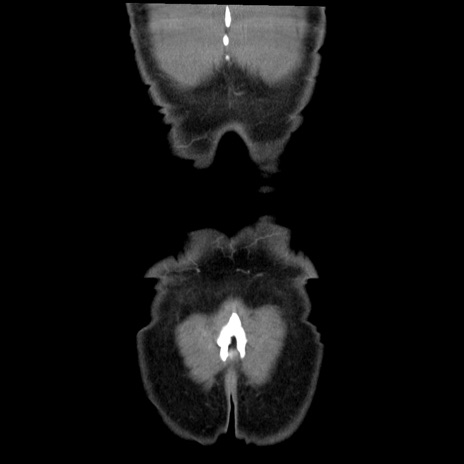

横断像